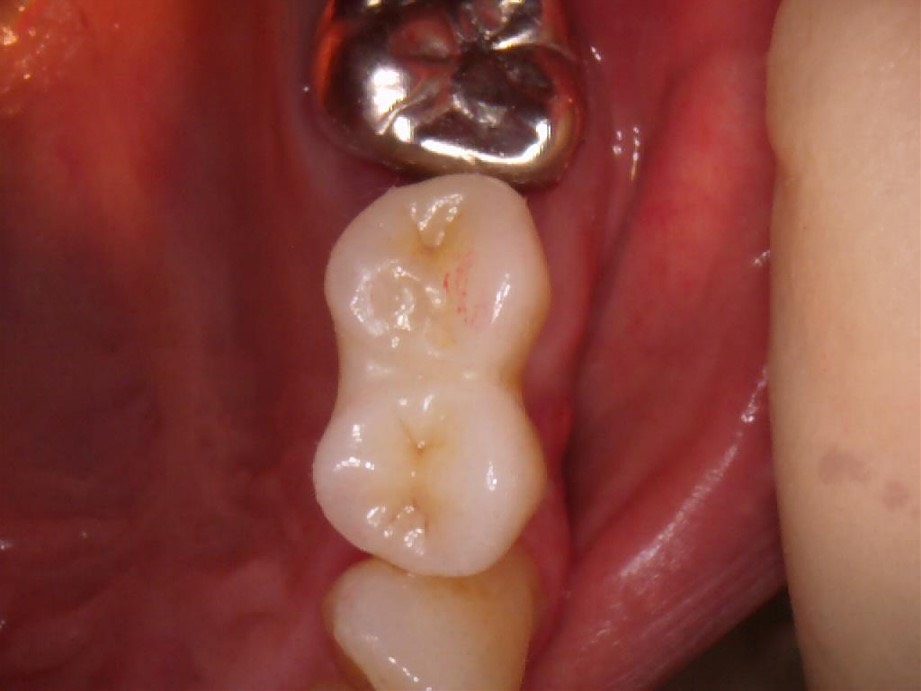

横から見た写真です。光が当たってるのでやや白く見えますが、実際はもう少し自然な仕上がりとなってます。